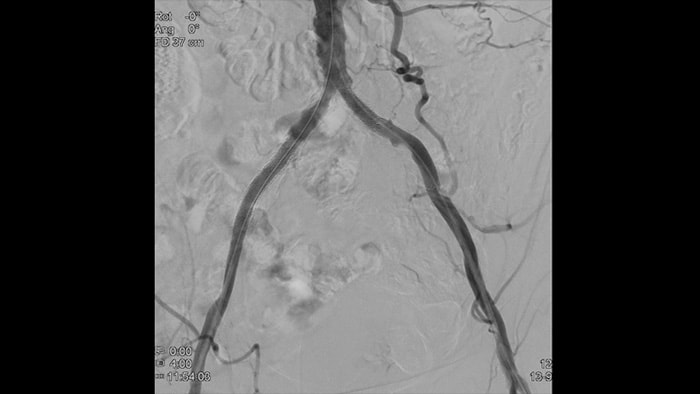

血管内超音波検査(IVUS)はカテーテルベースのイメージング技術であり、これを利用して医師は内部から血管を視覚化して、疾患の有無と程度を評価することができます。IVUSは、患者ごとに適切なインターベンション治療の選択、支援、そして確証に役立ちます。

血管の高精細画像は血管の細部まで鮮やかに捉えるため、正確な治療戦略、ナビゲーション、フォローアップをサポートします。